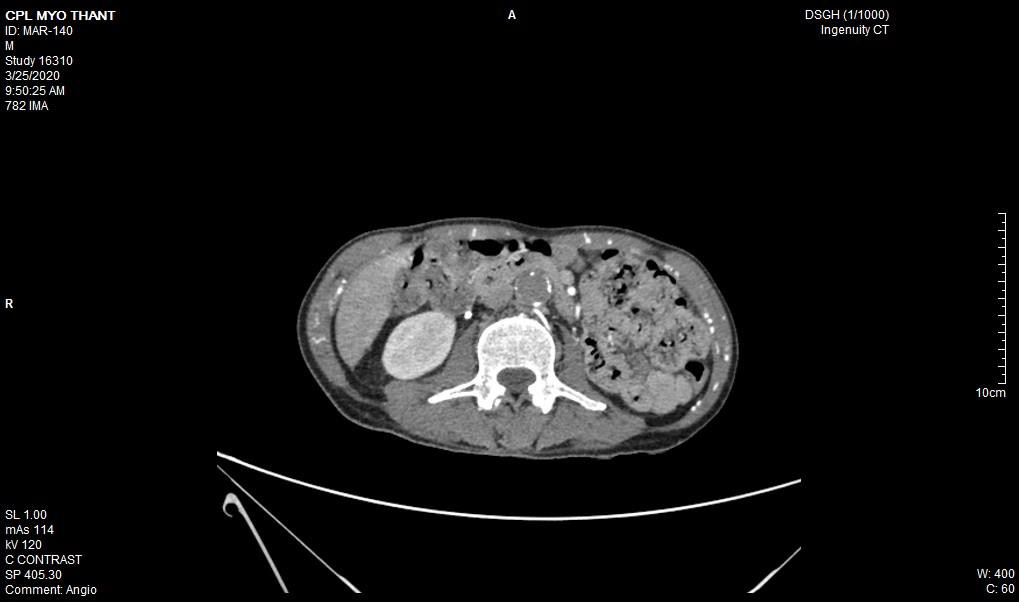

As his left femoral artery pulsation became weak and thus, CT Aortogram was done (4 weeks after symptom onset of right femoral artery occlusion). It revealed extensive thrombosis with complete obstruction of abdominal aorta starting below the level of celiac trunk- both renal arteries and both iliac arteries. The calcifications of the arterial wall at aortic arch, thoracic and abdominal aorta and both iliac vessels were seen too. (Figures 5-11) Thus, he had severe atherosclerosis due to hypertension and heavy smoking. Occlusion of both renal arteries explained his high blood pressure. The cholesterol and uric acid level were normal. He was treated with atorvastatin, aspirin, clopidogrel, antihypertensives, wound care, physiotherapy, intensive nursing care nutritional support and antibiotics.

This patient had on going ischaemia as the wound was not healing well and diminished left femoral pulsation. And it was a clinical clue to arterial obstruction at higher level – above femoral artery. It was proved by CT angiogram.

Regarding the aetiology of arterial occlusion in this 43-year-old patient, relatively young age, severe atherosclerosis was the main culprit as there were extensive atheromatous plaque in wall of the whole aorta and it was aggravated by smoking and hypertension. It was the main reason for reporting this case. Moreover, It was not due to COVID-19 infection because it was excluded initially though there were few case reports having deep vein thrombosis, pulmonary embolism and arterial thrombosis due to COVID-19 infection [11-13].

In essential thrombocythemia, recurrent thrombosis of same artery was seen in some cases [7,8]. Moreover, thrombosis at multiple site was reported too [14,2]. It commonly causes obstruction of small vessels and rarely to median and large arteries. Nevertheless, there were reports on essential thrombocythemia producing thrombosis of aorta [15-17]. In this case, combination of hypertension, smoking, severe atherosclerosis and essential thrombocythemia gave rise to extensive thrombosis of aorta; the rare variety of this case.